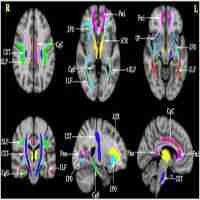

| Abstract | Alzheimer's Disease (AD) has long been considered a cortical degenerative disease, but impaired brain connectivity, due to white matter injury, may exacerbate cognitive problems. Predicting brain changes is critically important for early treatment. In a longitudinal diffusion tensor imaging study, we investigated white matter fiber integrity in 19 patients (mean age: 74.7 +/− 8.4 yrs at baseline) displaying early signs of mild cognitive impairment (eMCI). We first examined whether baseline average fractional anisotropy (FA) measures in the corpus callosum (CC) predicted changes in white matter integrity over the following 6 months. We then examined whether “small world” architecture measures — calculated from baseline connectivity maps — predicted white matter changes over the next 6 months. While average CC FA measures at baseline were not associated with future changes in FA, network measures were a sensitive biomarker for predicting white matter changes during this critical time before AD strikes. |